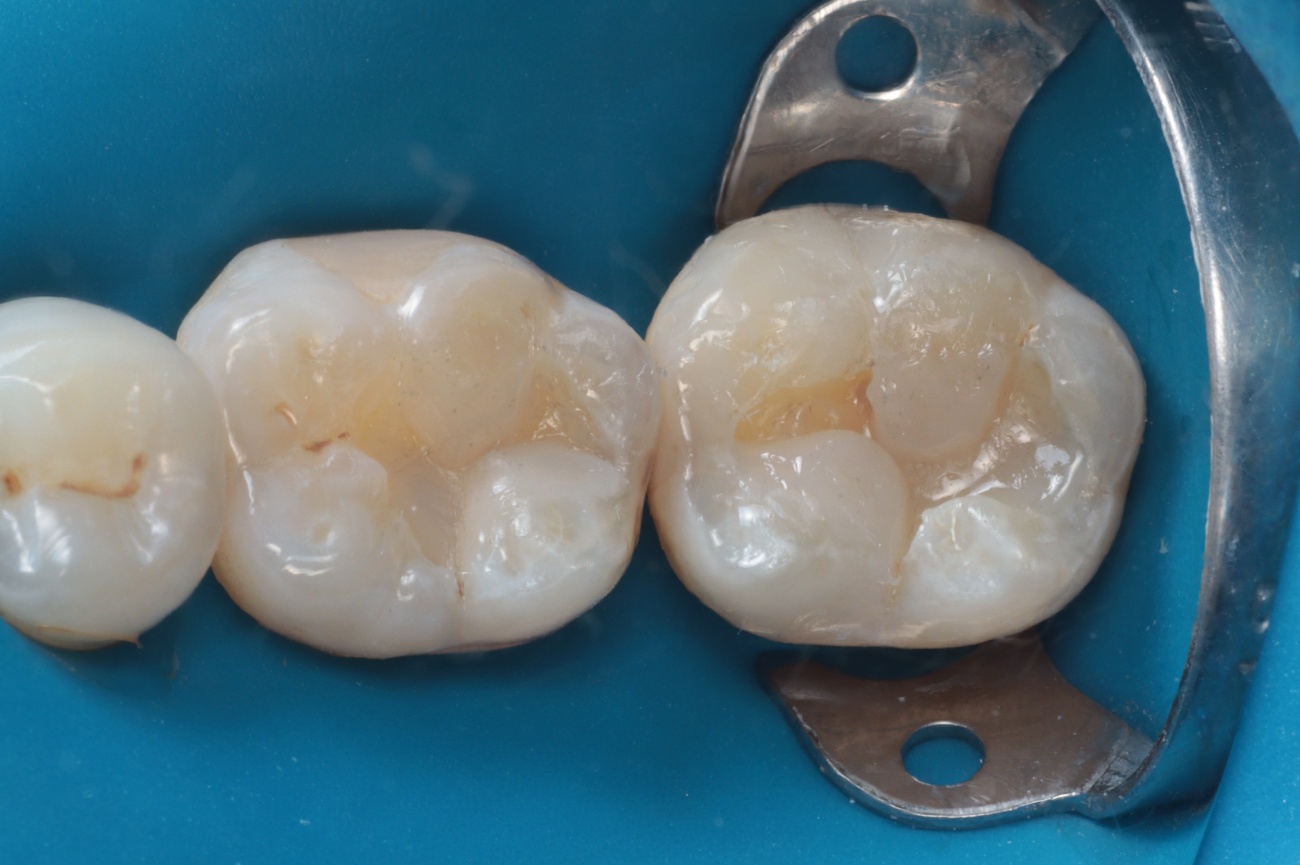

A reconstrução das cúspides e das faces oclusais foi realizada com a resina composta Luna 2 cor A2 (SDI), aplicada em incrementos de até 2 mm, seguindo a técnica de construção de cúspide a cúspide (Figura 8).

Figura 8 – reconstrução de cuspides